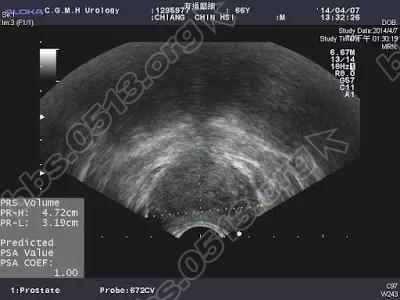

江先生,69岁男性,大约10年前已经接受过一次前列腺电切手术,刚开始尿的还不错。经过两三年后,排尿症状就又开始不好,排尿要先等一会才开始尿、腹部需要用力、憋尿后反而尿不出来、有时一尿急,来不及跑到厕所马上就尿在裤子上了,所以第一次开完刀后没有三五年后又开始与前列腺肥大药物为伍,也因为药物效果越来越差,江先生来到医院寻求协助, 前列腺彩超方面,体积勉强达到前列腺肥大的标准、看起来仅轻微突入到膀胱内、之前切除的沟槽也已经看不到了,但解尿的尿流速图形及残尿,显示还是有阻塞。